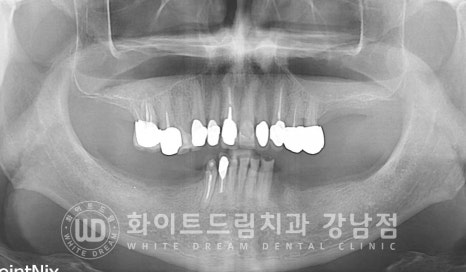

임플란트 개수를 줄여, 치료를 받으신 환자분의 치료 사례입니다.

상/하 양쪽 어금니가 모두 상실된 상태로 어금니 부분 틀니를 이용하여

식사를 진행하셨던 분입니다.

상실된 치아 부위가 많고 비용적인 부분을 크게 걱정하셨던 환자분이시기에

아직 받지 않으신 만 65세 건강보험 임플란트 혜택을 적용하여

임플란트 치료 계획을 세워드렸습니다.

상악은 오랜 기간 치아가 없는 채로 생활을 해오셨기에 잇몸뼈 흡수가 심하게 진행된 상태였습니다.